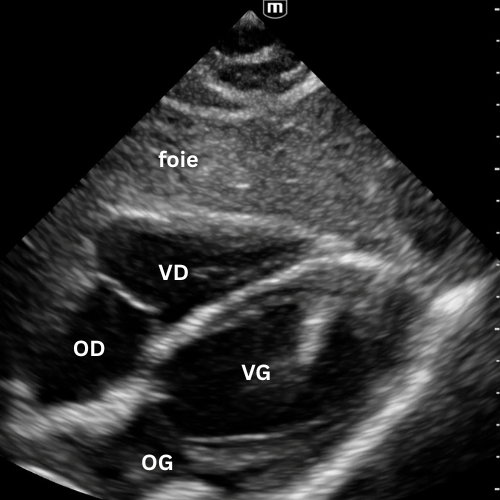

🔹 Vue Apicale Quatre Cavités

→ Quelle cavité domine ?

Placer la sonde près de l’apex (5e espace, région du mamelon gauche), marqueur vers l’épaule gauche. Glisse légèrement jusqu’à un bon espace intercostal, puis bascule la sonde vers la base du cœur jusqu’à voir VG, VD, OG et OD dans le même plan.

On visualise les quatre cavités, les valves mitrale et tricuspide et le septum.

Permet de comparer VD et VG (surcharge droite si VD ≥ VG), d’apprécier la cinétique globale et de repérer un épanchement péricardique circonférentiel.